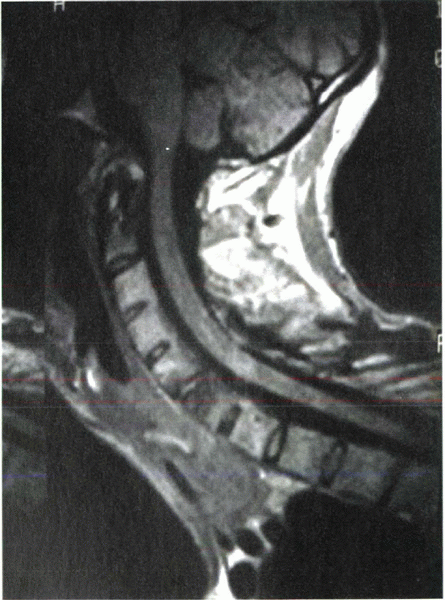

area of stenosis can be decompressed adequately (Fig. 23-3B). In addition, preoperative magnetic resonance imaging may be considered for complex cases (Fig. 23-4).

![]() |

|

Figure 23-4

Lateral magnetic resonance imaging of the cervical spine of a patient with cervical flexion deformity showing the spinal canal and cord. |